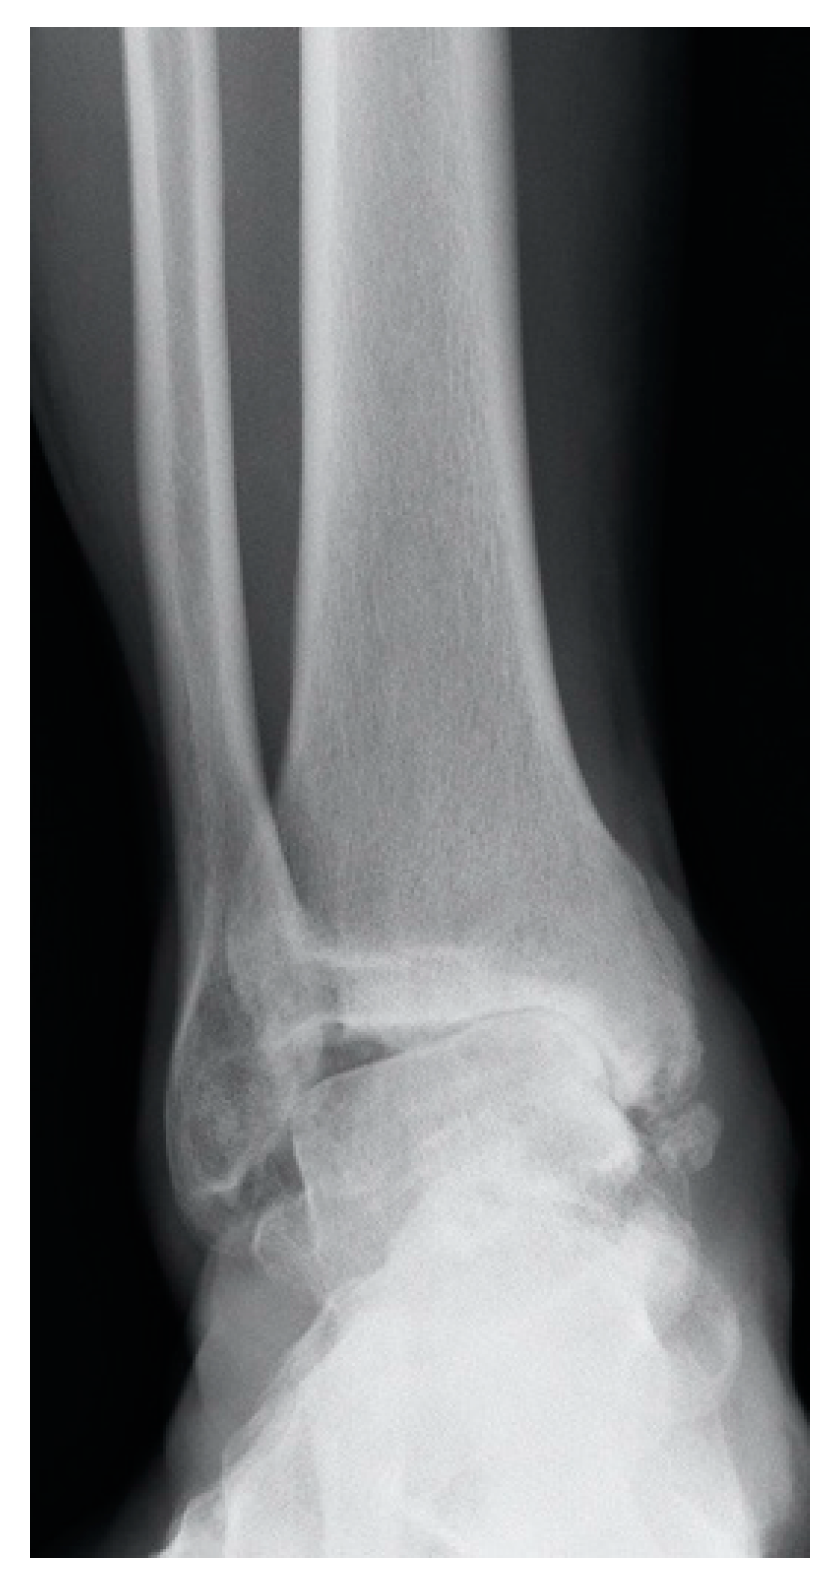

3.3. Joint Incongruence